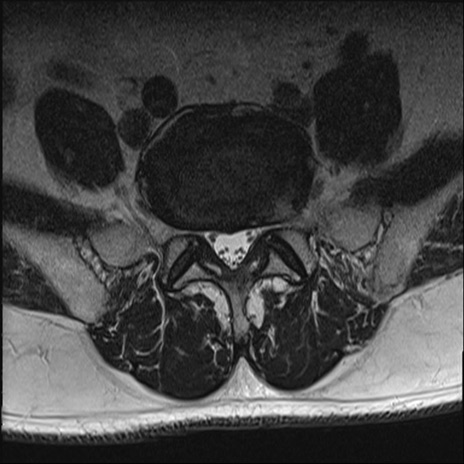

【整形】TIPS症例2 腰椎MRI T2WI(横断像)

【症例】70歳代男性

【主訴】左下肢痛

【現病歴】2週間前くらいから腰痛、左下肢痛あり。左臀部から大腿、下腿外側のしびれが常時ある。歩行とともに同部位の痛みあり。

【身体所見】Lasegue70-/60+、Bragard-/±、PTR ±/±、ATR -/-、IP 5/5、TA 5/4、TS 5/5、EHL 右第1足趾なし/3、FHL 5/5、hypersthesia(-)、足背動脈触知良好

異常所見と診断は?